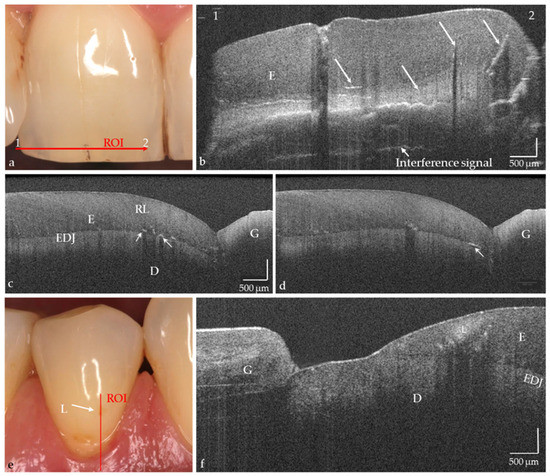

Caries, the world’s most common chronic disease, remains a major cause of invasive restorative dental treatment. To take advantage of the diagnostic potential of optical coherence tomography (OCT) in contemporary dental prevention and treatment, an intraorally applicable spectral-domain OCT probe has been developed [...] Read more.

Caries, the world’s most common chronic disease, remains a major cause of invasive restorative dental treatment. To take advantage of the diagnostic potential of optical coherence tomography (OCT) in contemporary dental prevention and treatment, an intraorally applicable spectral-domain OCT probe has been developed based on an OCT hand-held scanner equipped with a rigid 90°-optics endoscope. The probe was verified in vitro. In vivo, all tooth surfaces could be imaged with the OCT probe, except the vestibular surfaces of third molars and the proximal surface sections of molars within a "blind spot" at a distance greater than 2.5 mm from the tooth surface. Proximal surfaces of 64 posterior teeth of four volunteers were assessed by intraoral OCT, visual-tactile inspection, bitewing radiography and fiber-optic transillumination. The agreement in detecting healthy and carious surfaces varied greatly between OCT and established methods (18.2–94.7%), whereby the established methods could always be supplemented by OCT. Direct and indirect composite and ceramic restorations with inherent imperfections and failures of the tooth-restoration bond were imaged and qualitatively evaluated. The intraoral OCT probe proved to be a powerful technological approach for the non-invasive imaging of healthy and carious hard tooth tissues and gingiva as well as tooth-colored restorations. Full article